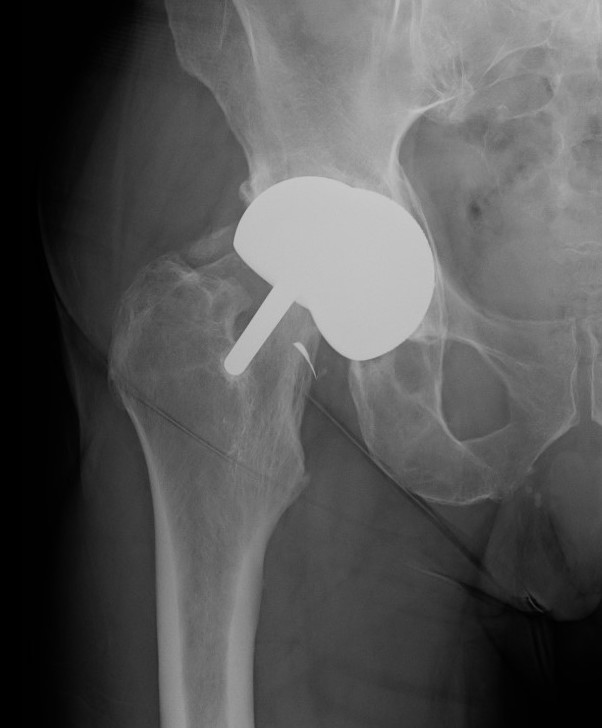

Femoral Neck Fracture

Risk Factors

- decreased bone mass / osteoporosis / elderly / inflammatory arthritis / AVN

- females

- femoral head and neck cysts

- femoral neck notching

- varus femoral component

Metallosis

Malloy et al JBJS Open Access 2024

- systematic review of 2,100 BHR at minimum 10 years

- 95% survival

- 20% of revisions for loosening, 20% for metal reaction

Aseptic loosening

Femoral head AVN

Due to extensive releases required to expose / surgically dislocate femoral head